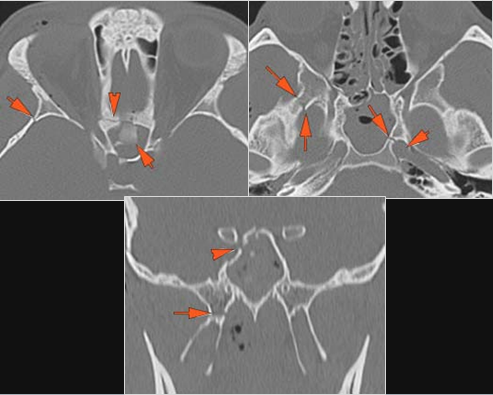

There is evidence of bony injury along the walls and/or floor of the orbit.

The supraorbital and infraorbital rims and orbital process of the zygoma and/or frontozygomatic suture are fractured.

The infraorbital canal is fractured.

The zygomatic arch is fractured.

The mesial naso-orbito-ethmoid complex is fractured. Specifically, there is bony injury of the nasal bones or the frontal process of the maxilla and the medial walls of the orbit are abnormal.

There is bony injury of the body, alveolar ridge, premaxilla, the infraorbital rim, the palatine or the frontal process of the maxillary bones on either side.

The pterygoid processes of the sphenoid bone are fractured.